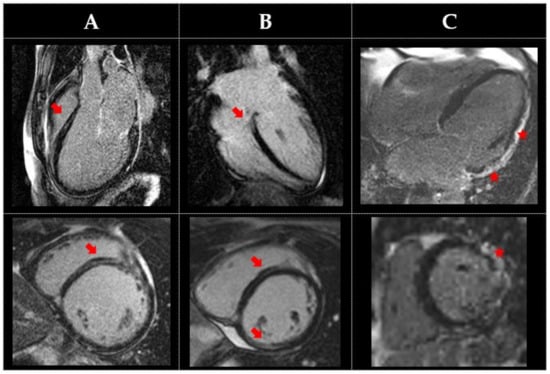

| Filamin C | Cardiac screening recommended in mutation-positive or first-degree relatives of proband Consider CMR Autosomal | Low voltage and flat or inverted T waves inferolaterally Early LGE with normal echo ECG features of ACM absent in ACM phenotype | DCM or ACM (LV) phenotype | Subepicardial or mid-myocardial inferolateral fibrosis “Ring-like” circumferential fibrosis, but not in all cases | Ventricular arrhythmias with a more marked and malignant course than average DCM cases | ||

| Desmin | Screening recommended Autosomal dominant CMR may be considered alongside ECG and Echo | Variable onset and prognosis depending on exact mutation | May or may not have skeletal muscle involvement | RCM, ACM, or DCM phenotype Focal wall hypertrophy early disease Oedema in acute phase Perfusion defect | Focal fibrosis by LGE (mid-wall or subepicardial) anywhere in LV (apex, anterior, septal, lateral, or inferior) or RV Transmural scar in advanced stage disease | AV conduction abnormalities and ventricular arrhythmias | |

| Danon | X-linked dominant | Syndromic facial features | HCM or DCM phenotype | LGE scar can be extensive and spares the mid-septum. High ECV/T1 | |||